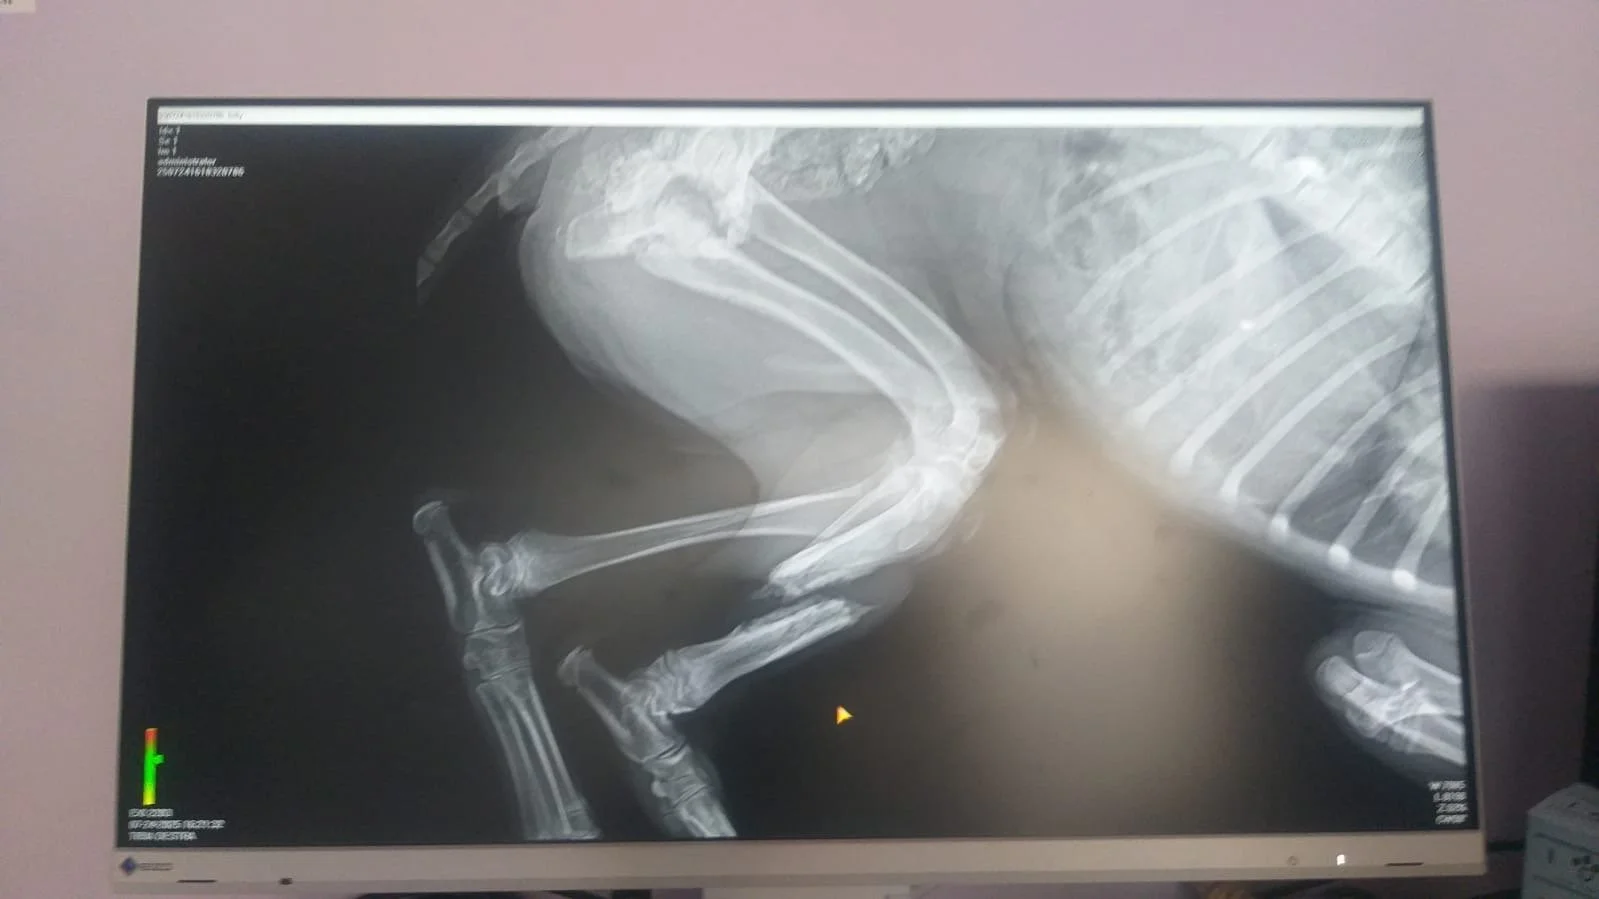

Nach einem zweiten Röntgen erklärte dieser Tierarzt, dass der Bruch von selbst verheilt sei.